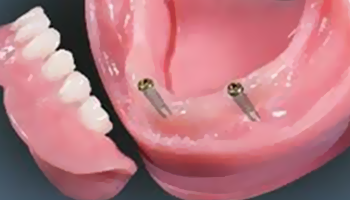

틀니 안쪽에 작은 고정장치가 있어

단추처럼 임플란트에 ‘딸깍’하고 끼워지는 구조라

일반 틀니보다 훨씬 덜 흔들리고 안정감이 좋습니다.